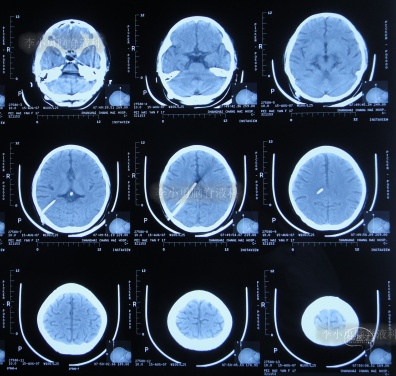

第2次脑室腹腔分流术后3月余即2007年8月15日,查头颅CT示未见异常(图-8)。

图-8:2007年8月15日头颅CT

于入院后2019年12月30日,进行了第3次进行了脑室腹腔分流术(分流阀初始压力2.0),仍保留了原2根脑室分流管;术后当天查头颅CT示脑室仍有扩张,脑室内有3根管(图-9)。

图-9:2019年12月30日头颅CT

第3次脑室腹腔分流术后1个月即2020年2月初,再次出现记忆力减退视物模糊,再过1个月仍无任何改善,于2020年3月17日(第3次脑室腹腔分流术后2个半月),到江苏省江阴某医院检查了头颅CT示脑室仍扩张(图-10)。

图-10:2020年3月17日头颅CT

2020年4月5日(第1次调压后18天),因症状持续不见减轻,到江苏省江阴某医院查头颅CT示脑室仍扩张(图-11)。

图-11:2020年4月5日头颅CT

但第2次调压仅2天后,症状又加重,到江苏省江阴某医院查头颅CT示脑室仍扩张(图-12)。为求进一步有效治疗,通过网络找到北京的李小勇脑脊液科。

图-12:2020年4月9日头颅CT